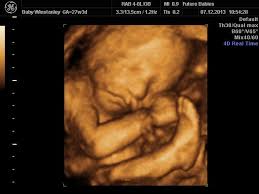

Come and see for yourlself. The best proof is our gallery of weekly 3d ultrasound images taken from 13 weeks and until up to 39 weeks. This page shows typical 3d ultrasound images from 11 to 36 weeks. All 3d ultrasound photos were taken in greenville sc at baby impressions. 18 week hd live/4d ultrasound. 3d/4d ultrasound march 31, 2021 | by kamrynlea has anyone gotten a 3d/4d ultrasound around 26/27 weeks? (so 31 weeks pregnant is the perfect time!) We do not perform medical ultrasounds. I have one scheduled and want to see some pics of what to expect!! At this stage, the baby has put on some weight and filled out to make features more visible, yet still enough fluid in front of baby's face to obtain great images. You're just dying to know what baby looks like inside your 31 weeks pregnant belly. Yawns, stretches, and even smiles are often captured in our 3d & 4d ultrasounds, and we look forward to sharing this miracle with you as well! Snuggling cord at 18 weeks.

It is a fun time for the ultrasound as many times you will see movements like smiling, eyes blinking, hands moving, and many other movements. If you are having multiples this is also a good time to capture 3d pictures of the babies. At this stage, the baby has put on some weight and filled out to make features more visible, yet still enough fluid in front of baby's face to obtain great images. Your baby has to hold very still so that the high frequency sound waves have time to form around your baby's features. Snuggling cord at 18 weeks. The 4d ultrasound uses sound waves to create this moving image. Up to 32 weeks there generally still room for the baby to move. Baby impressions is an elective 3d 4d ultrasound imaging facility. At 18 weeks, your baby has mastered the art of yawning, along with hiccuping, which you may feel soon. You learn today about your baby development, prenatal care (doctor visits) and fetal ultrasound at 31 weeks. I'm only at 31 weeks, but i had that 4d/3d u/s and yes, baby looked totally deformed. Sounds like you have a very active baby! We require that all mothers have documentation of their prenatal care and most recent diagnostic ultrasound.

At this stage, the baby has put on some weight and filled out to make features more visible, yet still enough fluid in front of baby's face to obtain great images. I'm only at 31 weeks, but i had that 4d/3d u/s and yes, baby looked totally deformed. We just went yesterday at 31 weeks 4 days. In fact, it's quite similar to 4d ultrasound. Up to 32 weeks there generally still room for the baby to move. View images & learn more 30 week ultrasound The 4d ultrasound uses sound waves to create this moving image. Sofort kostenlos und ohne anmeldung anfragen